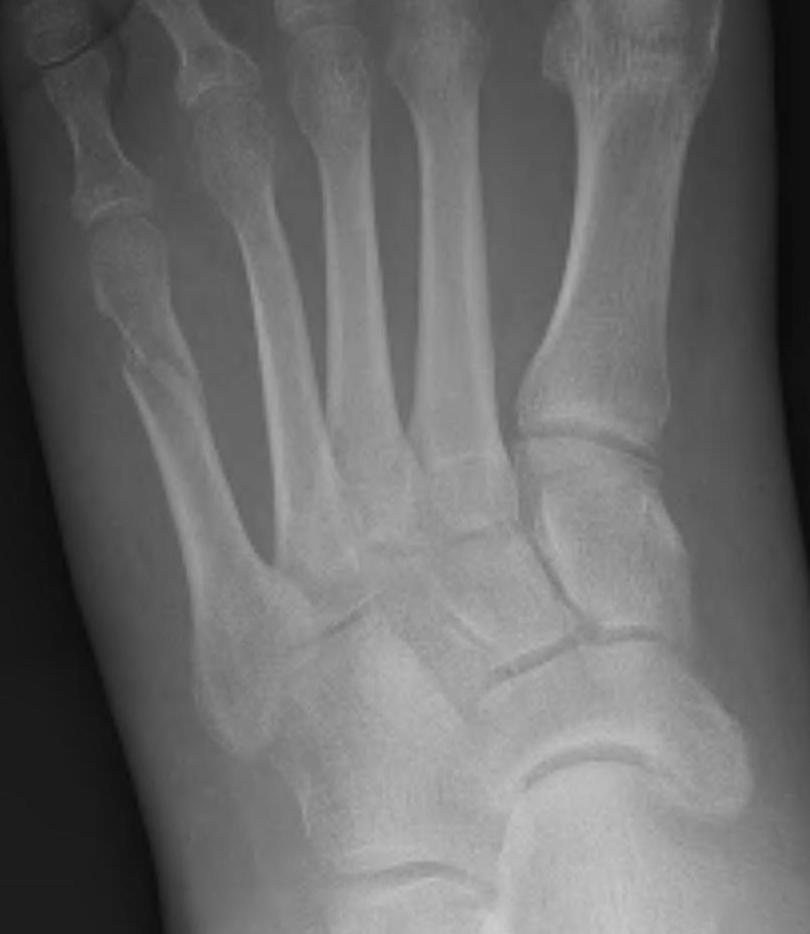

Base of 5th - Zone 1 / 2 / 3

Base Shaft Neck

Base of 5th metatarsal fractures

Classification

| Zone 1 | Zone 2 | Zone 3 |

|---|---|---|

|

Tuberosity avulsion fractures

Metaphyseal-diaphyseal junction Involves the 4th / 5th MT articulation |

Distal to the 4th / 5th MT articulation Proximal diaphysis |

| Inversion injuries |

Jones fracture Acute adduction injury |

Repetitive stress fracture Athletes |

![]() |

| Incidence: 93% | 4% | 3% |